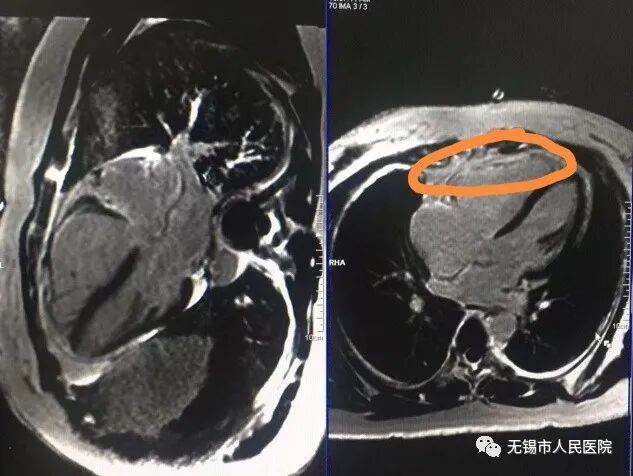

患者听到自己有心脏病感到非常的诧异!据她自己所述,之前在外院多次检查从未说过她心脏有问题,也没有觉得心脏有任何不适,并且已经生育两个孩子。但她还是听从了钱主任的建议,做了心脏核磁共振检查。核磁共振显示病人右室游离壁心肌缺失,取而代之的是脂肪纤维组织,最终证实了钱主任和过主任的判断。